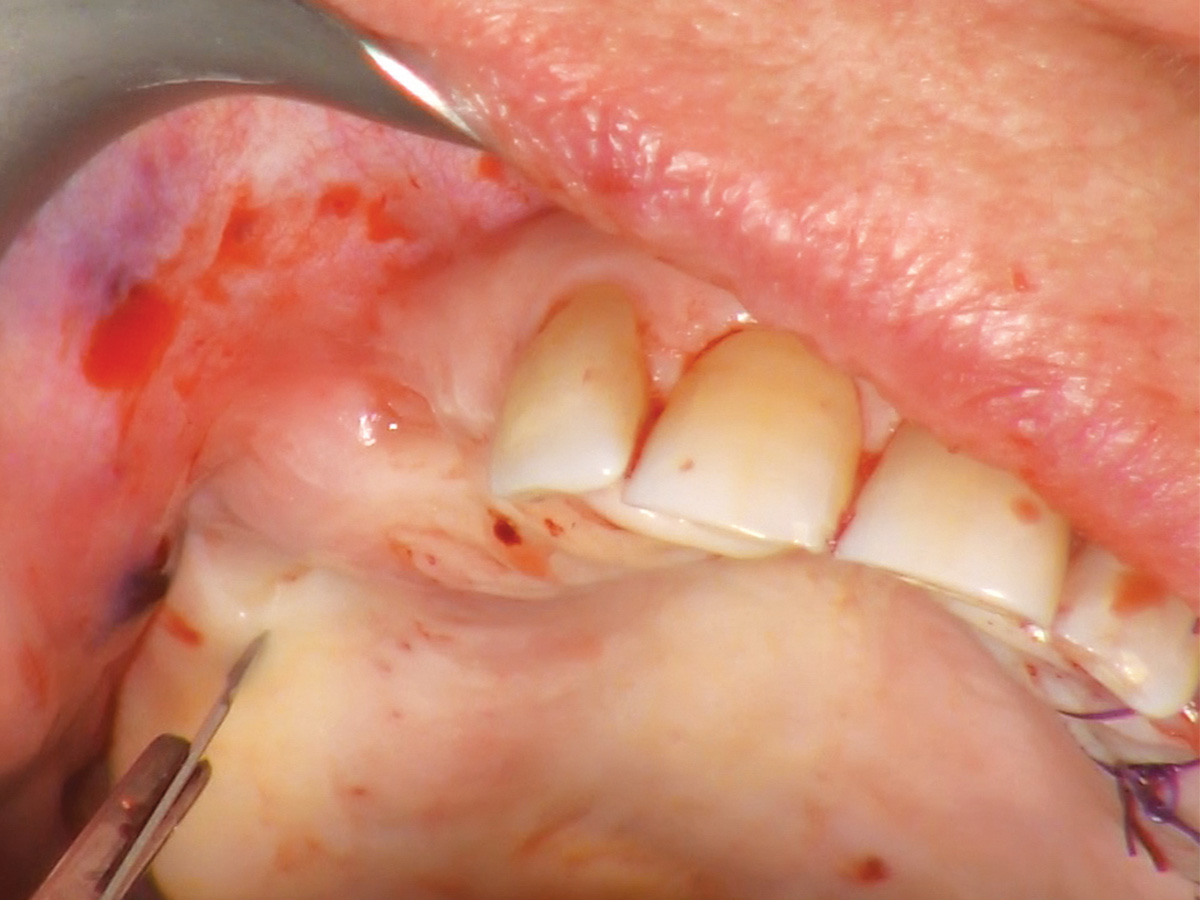

Abbildung 1

Die Versorgung dieses hochatrophen Oberkiefers erfordert einen Sinuslift.